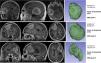

MethodsUnicentric retrospective observational study of a cohort of symptomatic meningiomas surgically removed in the time period between January 2015 and December 2022. Using specific segmentation software, the Surface Factor (SF) was calculated for each meningioma. SF is an objective parameter that compares the surface of a sphere (minimum surface area for a given volume) with the same volume of the tumour against the actual surface of the tumour. This ratio varies from 0 to 1, being 1 the maximum sphericity. Since irregularly-shaped meningiomas present proportionally greater surface area, the SF tends to decrease as irregularity increases. SF was correlated with WHO grade and its predictive power was estimated with ROC curve analysis.

ResultsA total of 176 patients (64.7% females) were included in the study; 120 WHO grade I (71.9%), 43 WHO grade II (25.7%) and 4 WHO grade III (2.4%). A statistically significant difference was found between the mean SF of WHO grade I and WHO grade II–III tumours (0.8651 ± 0.049 versus 0.7081 ± 0.105, p < 0.0001). Globally, the SF correctly classified more than 90% of cases (area under ROC curve 0.940) with 93.3% sensibility and 80.9% specificity. A cutoff value of 0.79 yielded the maximum precision, with positive and negative predictive powers of 82.6% and 92.6%, respectively. Multivariate analysis yielded SF as an independent prognostic factor of WHO grade.

ConclusionThe Surface Factor is an objective and quantitative parameter that helps to identify aggressive meningiomas preoperatively. A cutoff value of 0.79 allowed differentiation between WHO grade I and WHO grade II–III with high precision.